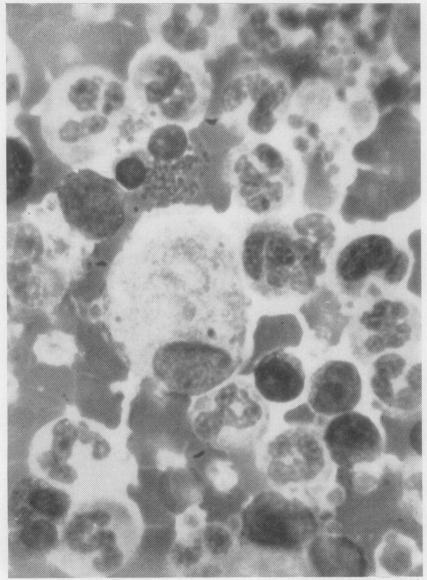

White-cell concentrates were made by a dextran sedimentation technique from the blood of 140 cases of malignant disease and 60 controls. The slides were searched for tumour cells and for other unusual cells with which they might be confused. Several million white cells were scanned in the slides from each case. Acceptable tumour cells were identified in the blood of seven patients, none of whom survived for more than a few months. These cells are illustrated, as well as various other cell types which may have been confused with malignant cells in the past. It is concluded that the cytology of white cell concentrates should be further explored before statistics about the occurrence of circulating tumour cells are accepted.

采用葡聚糖沉降技术从140例恶性疾病患者及60例对照者的血液中制备白细胞浓缩物。在玻片上查找肿瘤细胞以及可能与之混淆的其他异常细胞。对每个病例的玻片扫描数百万个白细胞。在7名患者的血液中鉴定出了可接受的肿瘤细胞,其中无一例存活超过几个月。文中展示了这些细胞以及过去可能与恶性细胞混淆的各种其他细胞类型。得出的结论是,在接受关于循环肿瘤细胞发生率的统计数据之前,应进一步探索白细胞浓缩物的细胞学。